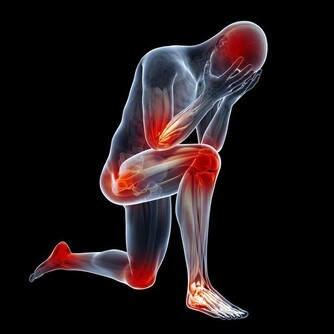

失智症年輕化 早期徵兆不可輕忽

一位正值人生顛峰時刻的大學教授,卻被診斷出罹患了早發性的阿茲海默症。

當她一步步退­化,家人和同事的關係也跟著改變。

目前還沒有任何藥物可以治癒失智症,

但卻可以靠後天的努力,來延緩完全發作與退化的時­機。

患者應養成終身學習的習慣,搭配規律地運動及健康飲食,

在家人的陪伴下積極再次走­入人群,也許一切都像未曾發生過。